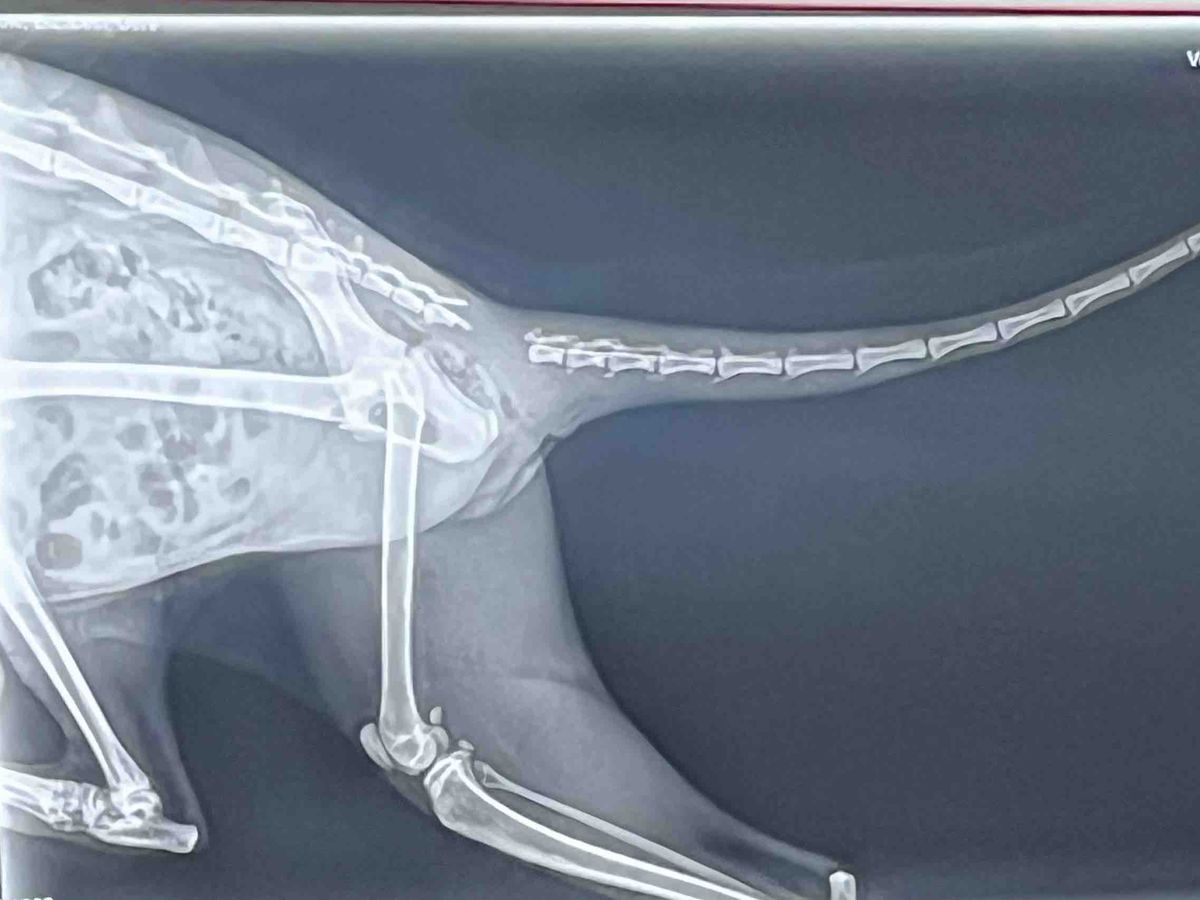

She was found alone and wounded with a useless tail at Bona Dea on Tuesday, December 2nd. We got her to the vet on the 5th and found out, while the outside skin seemed okay, the skeletal base of her tail had been ripped from her spinal cord, rendering it permanently disabled and prone to infection. Thus, it has to be amputated.

Her amputation is already scheduled for Friday, December 12th. Any donations to alleviate the costs would be greatly appreciated! We have already spent about $300 for an x-ray and all her vaccinations… her amputation itself is estimated to be about $220, but the medications and any complications can raise that. (The disconnect is in a very “inconvenient” spot, which can cause complications.)